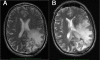

Methods: 10 patients with advanced recurrent anaplastic astrocytoma (n = 2) or glioblastoma (n = 8) aged 32-62 years were recruited prior to the planned interim analysis of the study. Subjects were randomly assigned to daily doses of 1. 5, 3, 4 V体育安卓版. 5, or 6 grams of oral sulfasalazine, and treated until clinical or radiological evidence of disease progression or the development of serious or unbearable side effects. Primary endpoints were the evaluation of toxicities according to the CTCAE v. 3. 0, and the observation of radiological tumor responses based on MacDonald criteria. .

Results: No clinical response was observed V体育ios版. One tumor remained stable for 2 months with sulfasalazine treatment, at the lowest daily dose of the drug. The median progression-free survival was 32 days. Side effects were common, as all patients developed grade 1-3 adverse events (mean: 7. 2/patient), four patients developed grade 4 toxicity. Two patients died while on treatment or shortly after its discontinuation. .